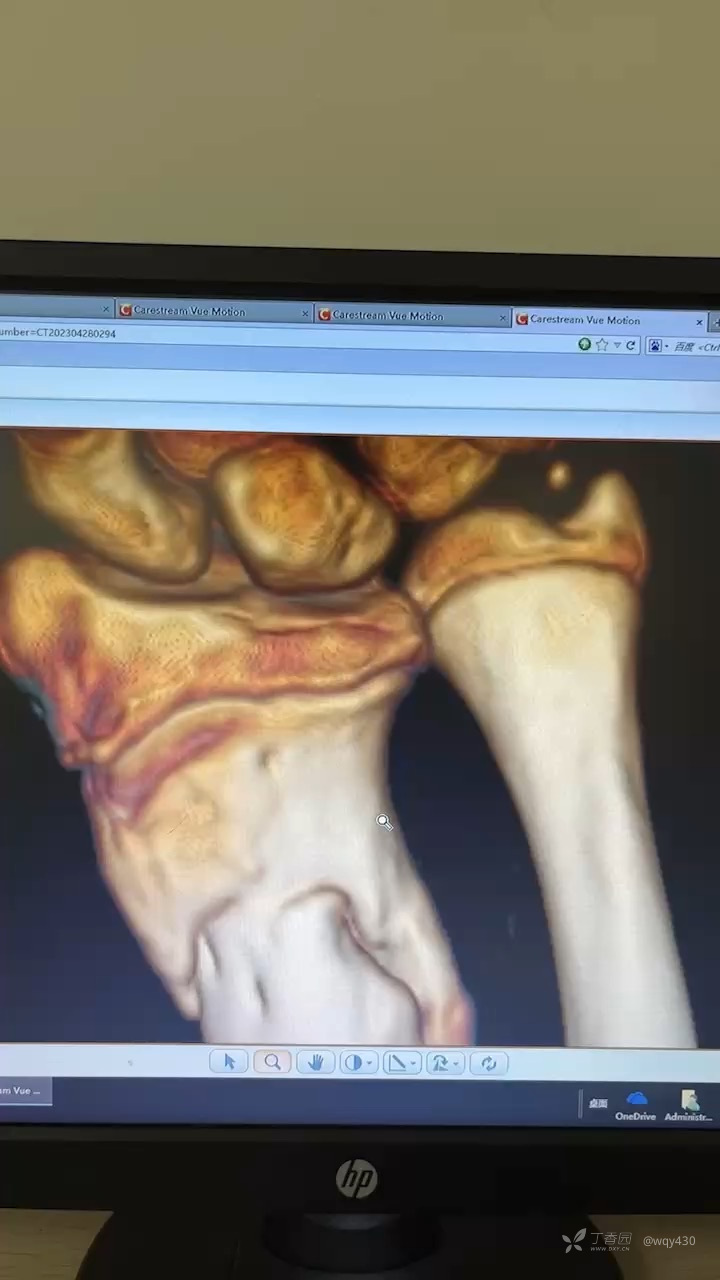

患儿,男,13岁,摔伤致伤,行手术治疗克氏针固定,术后2月骨折愈合不良,求进一步治疗方案:

下面是术后约10

求下一步治疗方案1再次内固定,钢板or克氏针

2外固定架3先姑息观察,进一步再手术